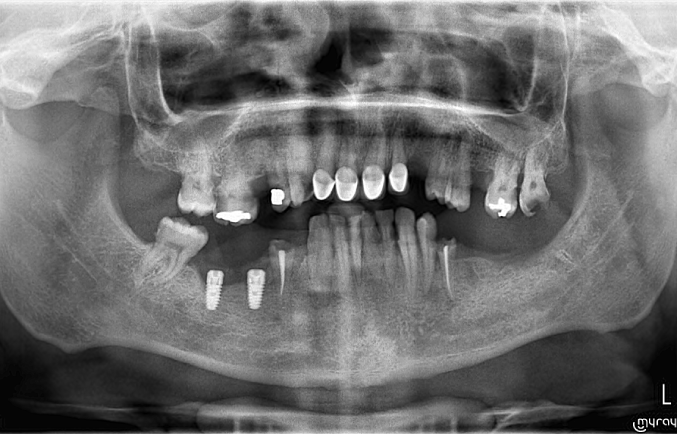

Cas 1

Traitement implantaire bouche complète

Cas 2

Traitement implantaire bouche complète

Cas 3

Traitement implantaire bouche complète

Cas 4

Traitement implantaire bouche complète

Cas 5

Traitement implantaire bouche complète

Cas 6

Traitement implantaire bouche complète

Cas 7

Traitement implantaire bouche complète

Cas 8

Traitement implantaire bouche complète